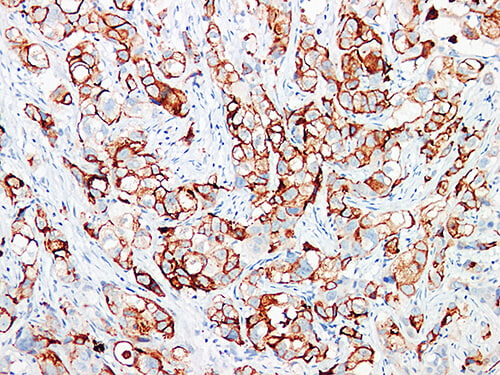

The GCDFP-15 (Gross Cystic Disease Fluid Protein-15) Antibody is a highly specific

immunohistochemical marker used to identify apocrine-differentiated breast carcinomas.

In pathology, GCDFP-15 shows strong cytoplasmic staining in breast adenocarcinomas.

Meanwhile, it is usually negative in lung, colorectal, and mesothelial tumors.

- Clear brown cytoplasmic staining in positive cells